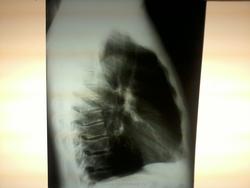

Мужчина, 50 лет. Дообследование после флюорографии. В проекции в/д правого легкого определяется гомогенное образование, с четким контуром, широким основанием прилегающее к тени средостения. На правом боковом снимке ОГК четко образование не определяется. Предполагаю наличие образования из средостения (если придерживаться правилам Ленка и Зенихиной). Хотелось бы узнать ваши мнения по данным снимкам. Заранее извиняюсь за качество, фотографии были сделаны на сотовый телефон.

Мне в 6 сегменте справа не нравится кольцевидная тень ! В прямой - она мало заметна , малоинтенсивна , а в боковой- очень даже видна . А на счет тени у средостения - да , нужно "докрутить " ( или скопически , или заднюю + косую)

Думаю, кольцевидная тень - скиалогия. Тоже сначала глаз зацепился, но потом как-то "рассыпалась" на элементы легочного рисунка. Да и такого характера истинное затемнение было бы и на прямом. На скопии (если будет) сразу будет понятно.